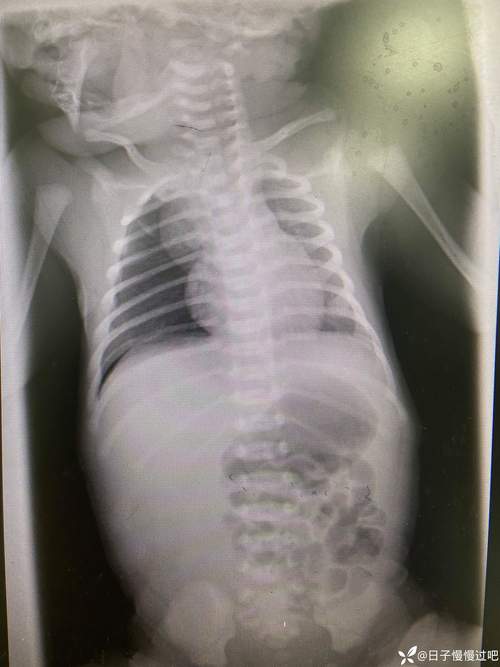

- 及时就医:一旦发现宝宝有呼吸异常、喂养困难或“三凹征”等情况,应立即带宝宝去医院儿科或新生儿科就诊,医生会通过听诊、X光、CT或支气管镜等检查来明确诊断。